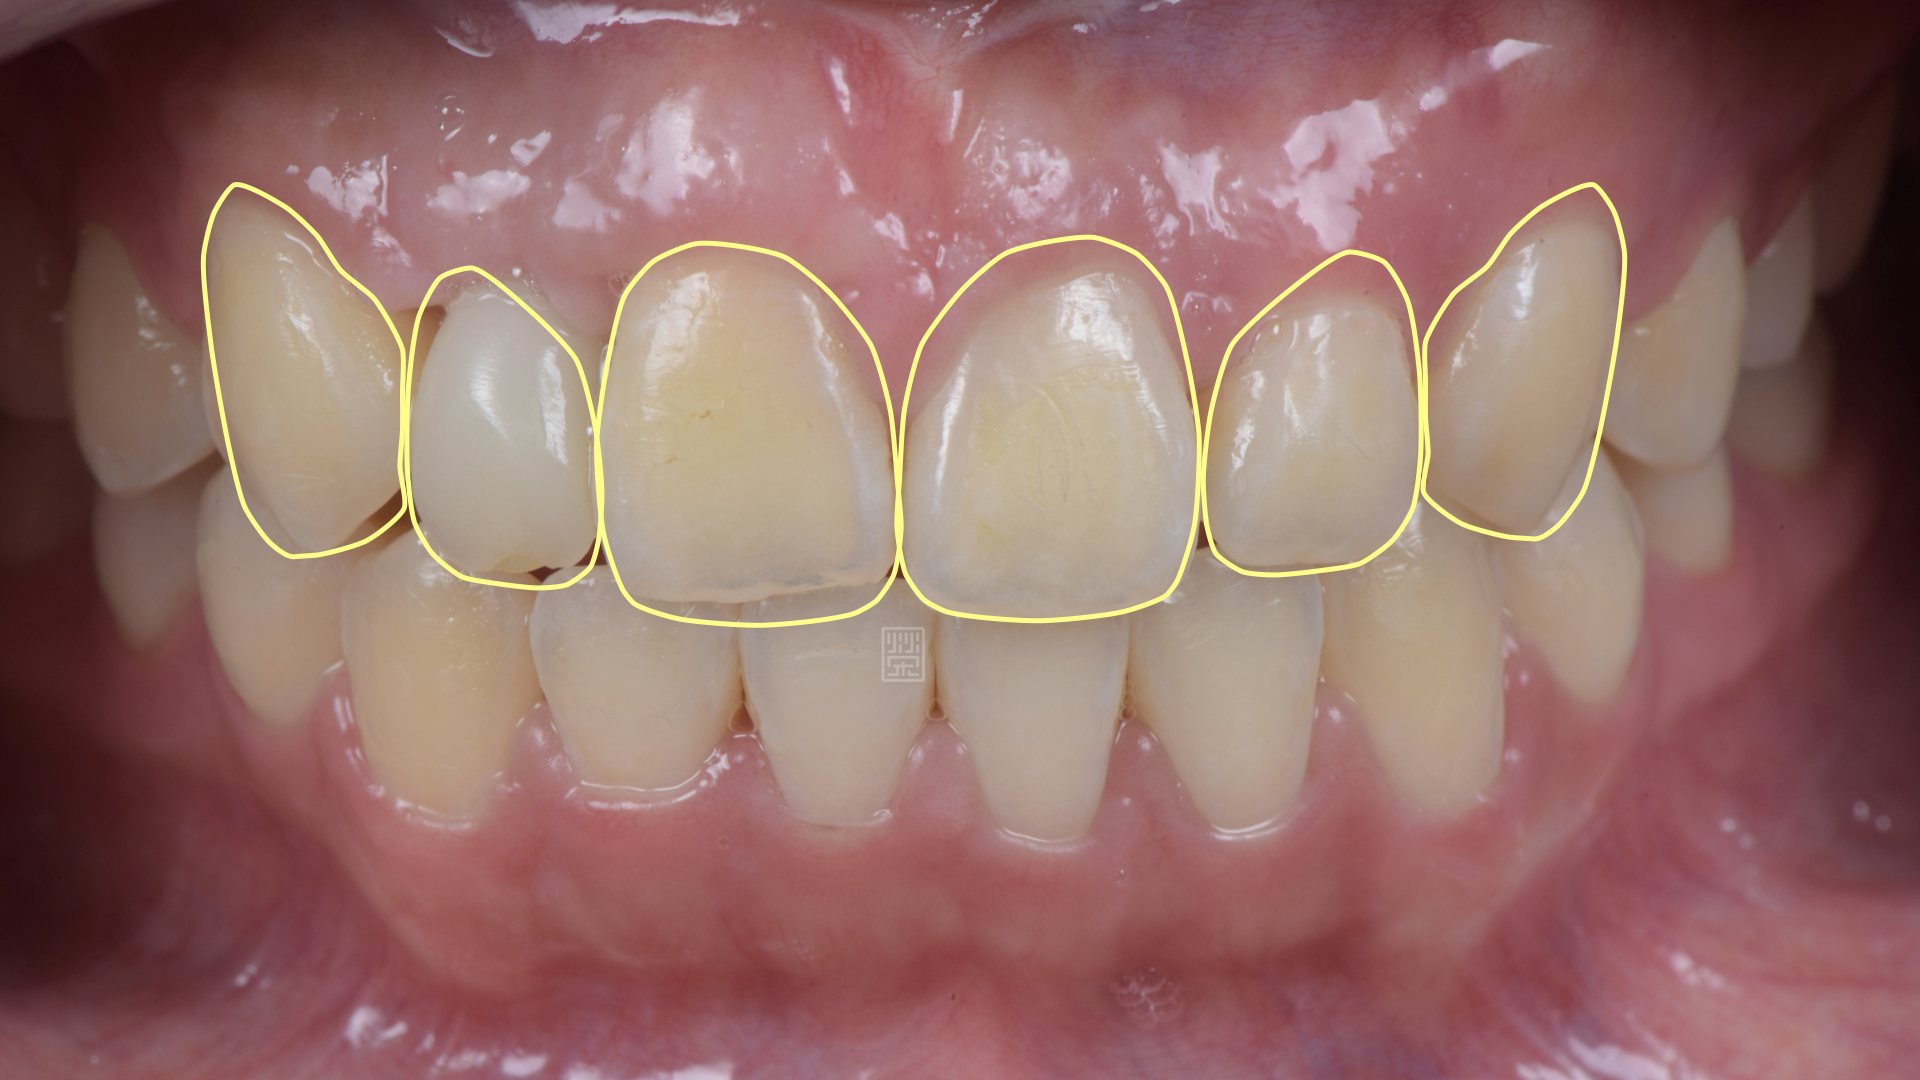

由於門牙本身偏短,藉由微笑分析,決定由牙冠增長術與改變牙齒長度讓門牙達到更好的比例與對稱性,加上側門牙植牙牙齦的調整,並且將右側犬齒用全瓷冠恢復犬齒導引,達到保護性咬合,對未來咬合性穩定性更有幫助。

全瓷冠位置、牙齦線位置評估